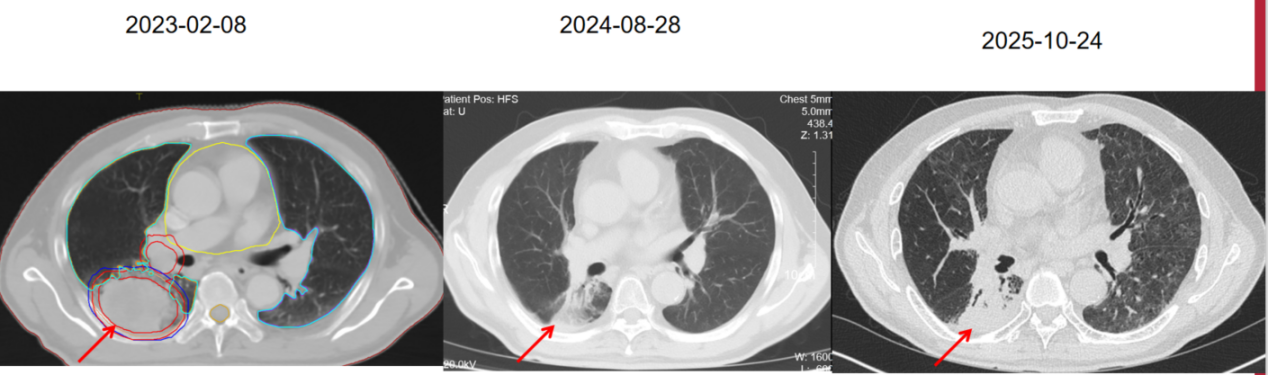

2023-02-09始行胸部病灶放疗,处方剂量: PTV-boost 6MV-X,DT 5400cGy/25fx/5w, PTV 6MV-X,DT 5000cGy/25fx/5w。二程肿瘤中心区域局部加量:PTVboost 6MV-X,DT 1000cGy/2fx/1w。

后续舒格利单抗 1200mg d1 q3W免疫治疗维持至今。疗效评价PR。颅脑MRI未见肿瘤复发进展。